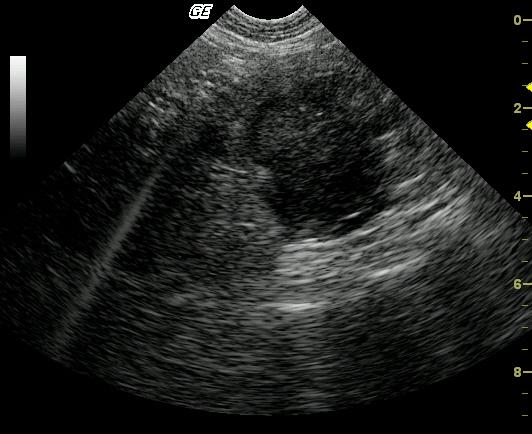

This 16-year-old FS DSH was presented for chronic vomiting, lethargy, anorexia, PU/PD, and weight loss. The clinical exam revealed moderate dehydration and mild hyperthermia. The CBC and blood chemistry analysis was normal except for a minor SAP elevation.